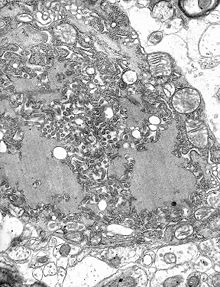

TEM micrograph with numerous rabies virions (small, dark grey, rodlike particles) and Negri bodies (the larger pathognomonic cellular inclusions of rabies infection)

The rabies virus is the type species of the Lyssavirus genus, in the family Rhabdoviridae, order Mononegavirales. Lyssaviruses have helical symmetry, with a length of about 180  nm and a cross-section of about 75 nm. These viruses are enveloped and have a single-stranded RNA genome with negative sense. The genetic information is packed as a ribonucleoprotein complex in which RNA is tightly bound by the viral nucleoprotein. The RNA genome of the virus encodes five genes whose order is highly conserved: nucleoprotein (N), phosphoprotein (P), matrix protein (M), glycoprotein (G), and the viral RNA polymerase (L).